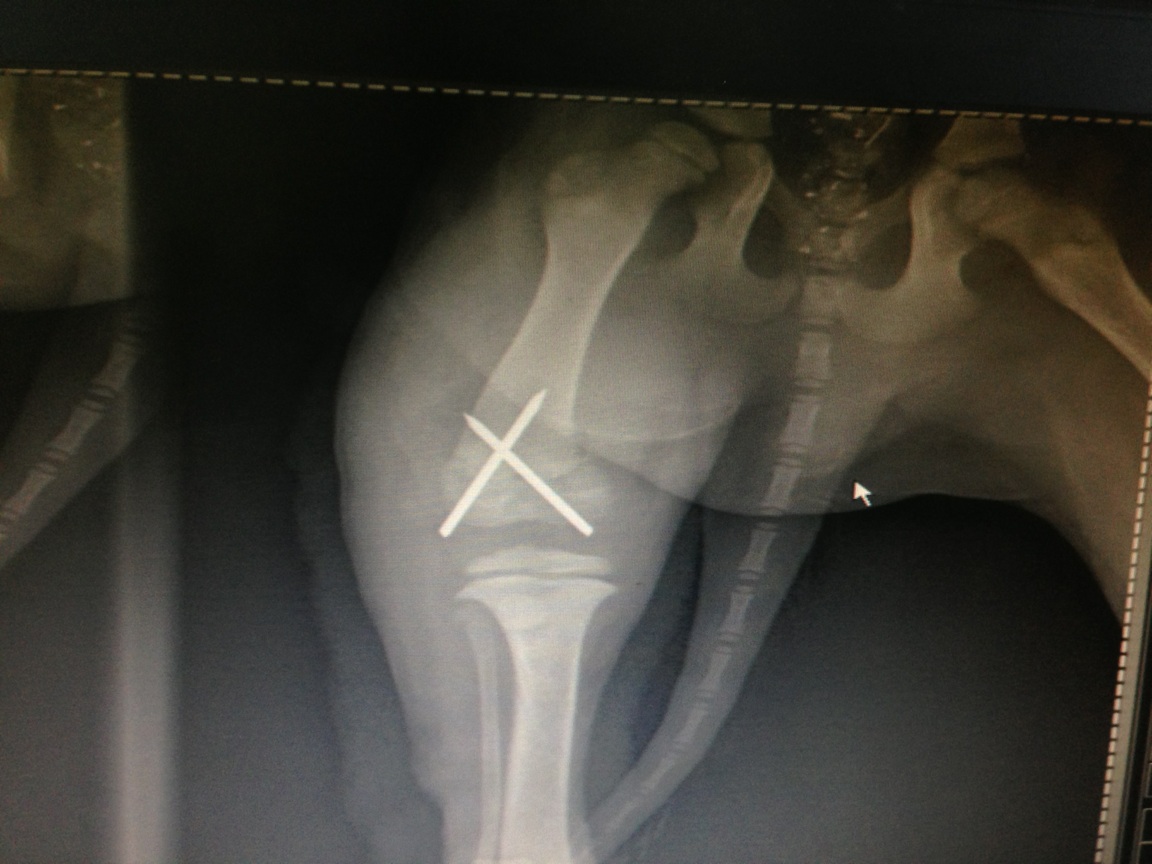

Distal Radius Fracture in back right leg when it was ran over in a “Hit & Run” accident last Friday evening in Rawang. (Attached Image 3 as the X-ray)Healing Treatments:

A) To undergo Percutaneous Pinning surgery and input a cross pin onto the fractured part. This will be done by the vet you recommended.

B) If no surgery is done, high risk outcome which may cause Leg Length Inequality and also Joint Stiffness that will affect the dog’s future movements.I have immediately agreed to proceed for the surgery to avoid any suffering for the dog in future. The dog is currently kept at the clinic and the vet had arranged to undergo it tomorrow (Monday) and it should be able to discharge by Wed/Thur. Total fee is still yet to be confirmed but it will range in RM800-RM850 for all the cost of the surgery (Anesthesia, Manipulation, medicines), X-ray, Boarding Fee.